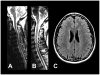

Magnetic resonance imaging (MRI) has led to the identification of widespread brain abnormalities in multiple sclerosis (MS) that extend far beyond the classic white matter lesion. These findings have generated the idea that MS should be understood as a disease of the whole brain, not just the white matter. While it is no doubt the case that many different pathways are ultimately involved in the destruction of brain tissue that occurs in MS, the implications of the accumulated evidence for understanding disease pathophysiology - and hence the overall significance of these imaging findings - are doubtful. Here, I argue that the principled use of imaging can, in fact, address questions about the genesis of these whole-brain abnormalities, rather than simply describe them.